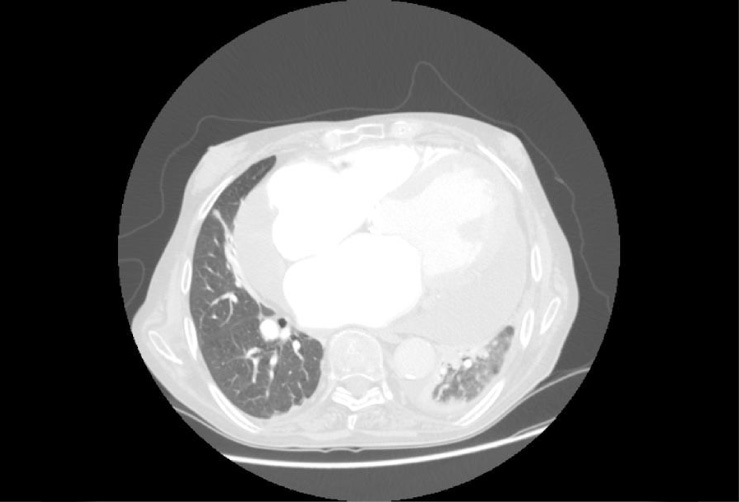

L’ecocardiogramma trans-toracico mostrava FE = 28%, versamento pericardico prevalente a carico della parete libera del ventricolo sinistro e posteriormente, con scollamento massimo di 4 cm, senza segni di tamponamento; discreto aumento della pressione arteriosa polmonare (PAP) a 45-50 mmHg. Dalla TAC torace erano visibili cardiomegalia, abbondante versamento pericardico, discreto versamento pleurico a sinistra con atelettasia parziale del lobo inferiore, alterazioni parenchimali bilaterali con aspetto a vetro smerigliato e qualche linfonodo mediastinico con diametro < 1 cm (Figure 4 e 5).

Figura 4. TAC torace (aprile 2012): cardiomegalia, abbondante versamento pericardico, discreto versamento pleurico a sinistra con atelettasia parziale del lobo inferiore, alterazioni parenchimali bilaterali con aspetto a vetro smerigliato, qualche linfonodo mediastinico con diametro < 1 cm

Figura 5. TAC torace (aprile 2012): particolare per il parenchima polmonare